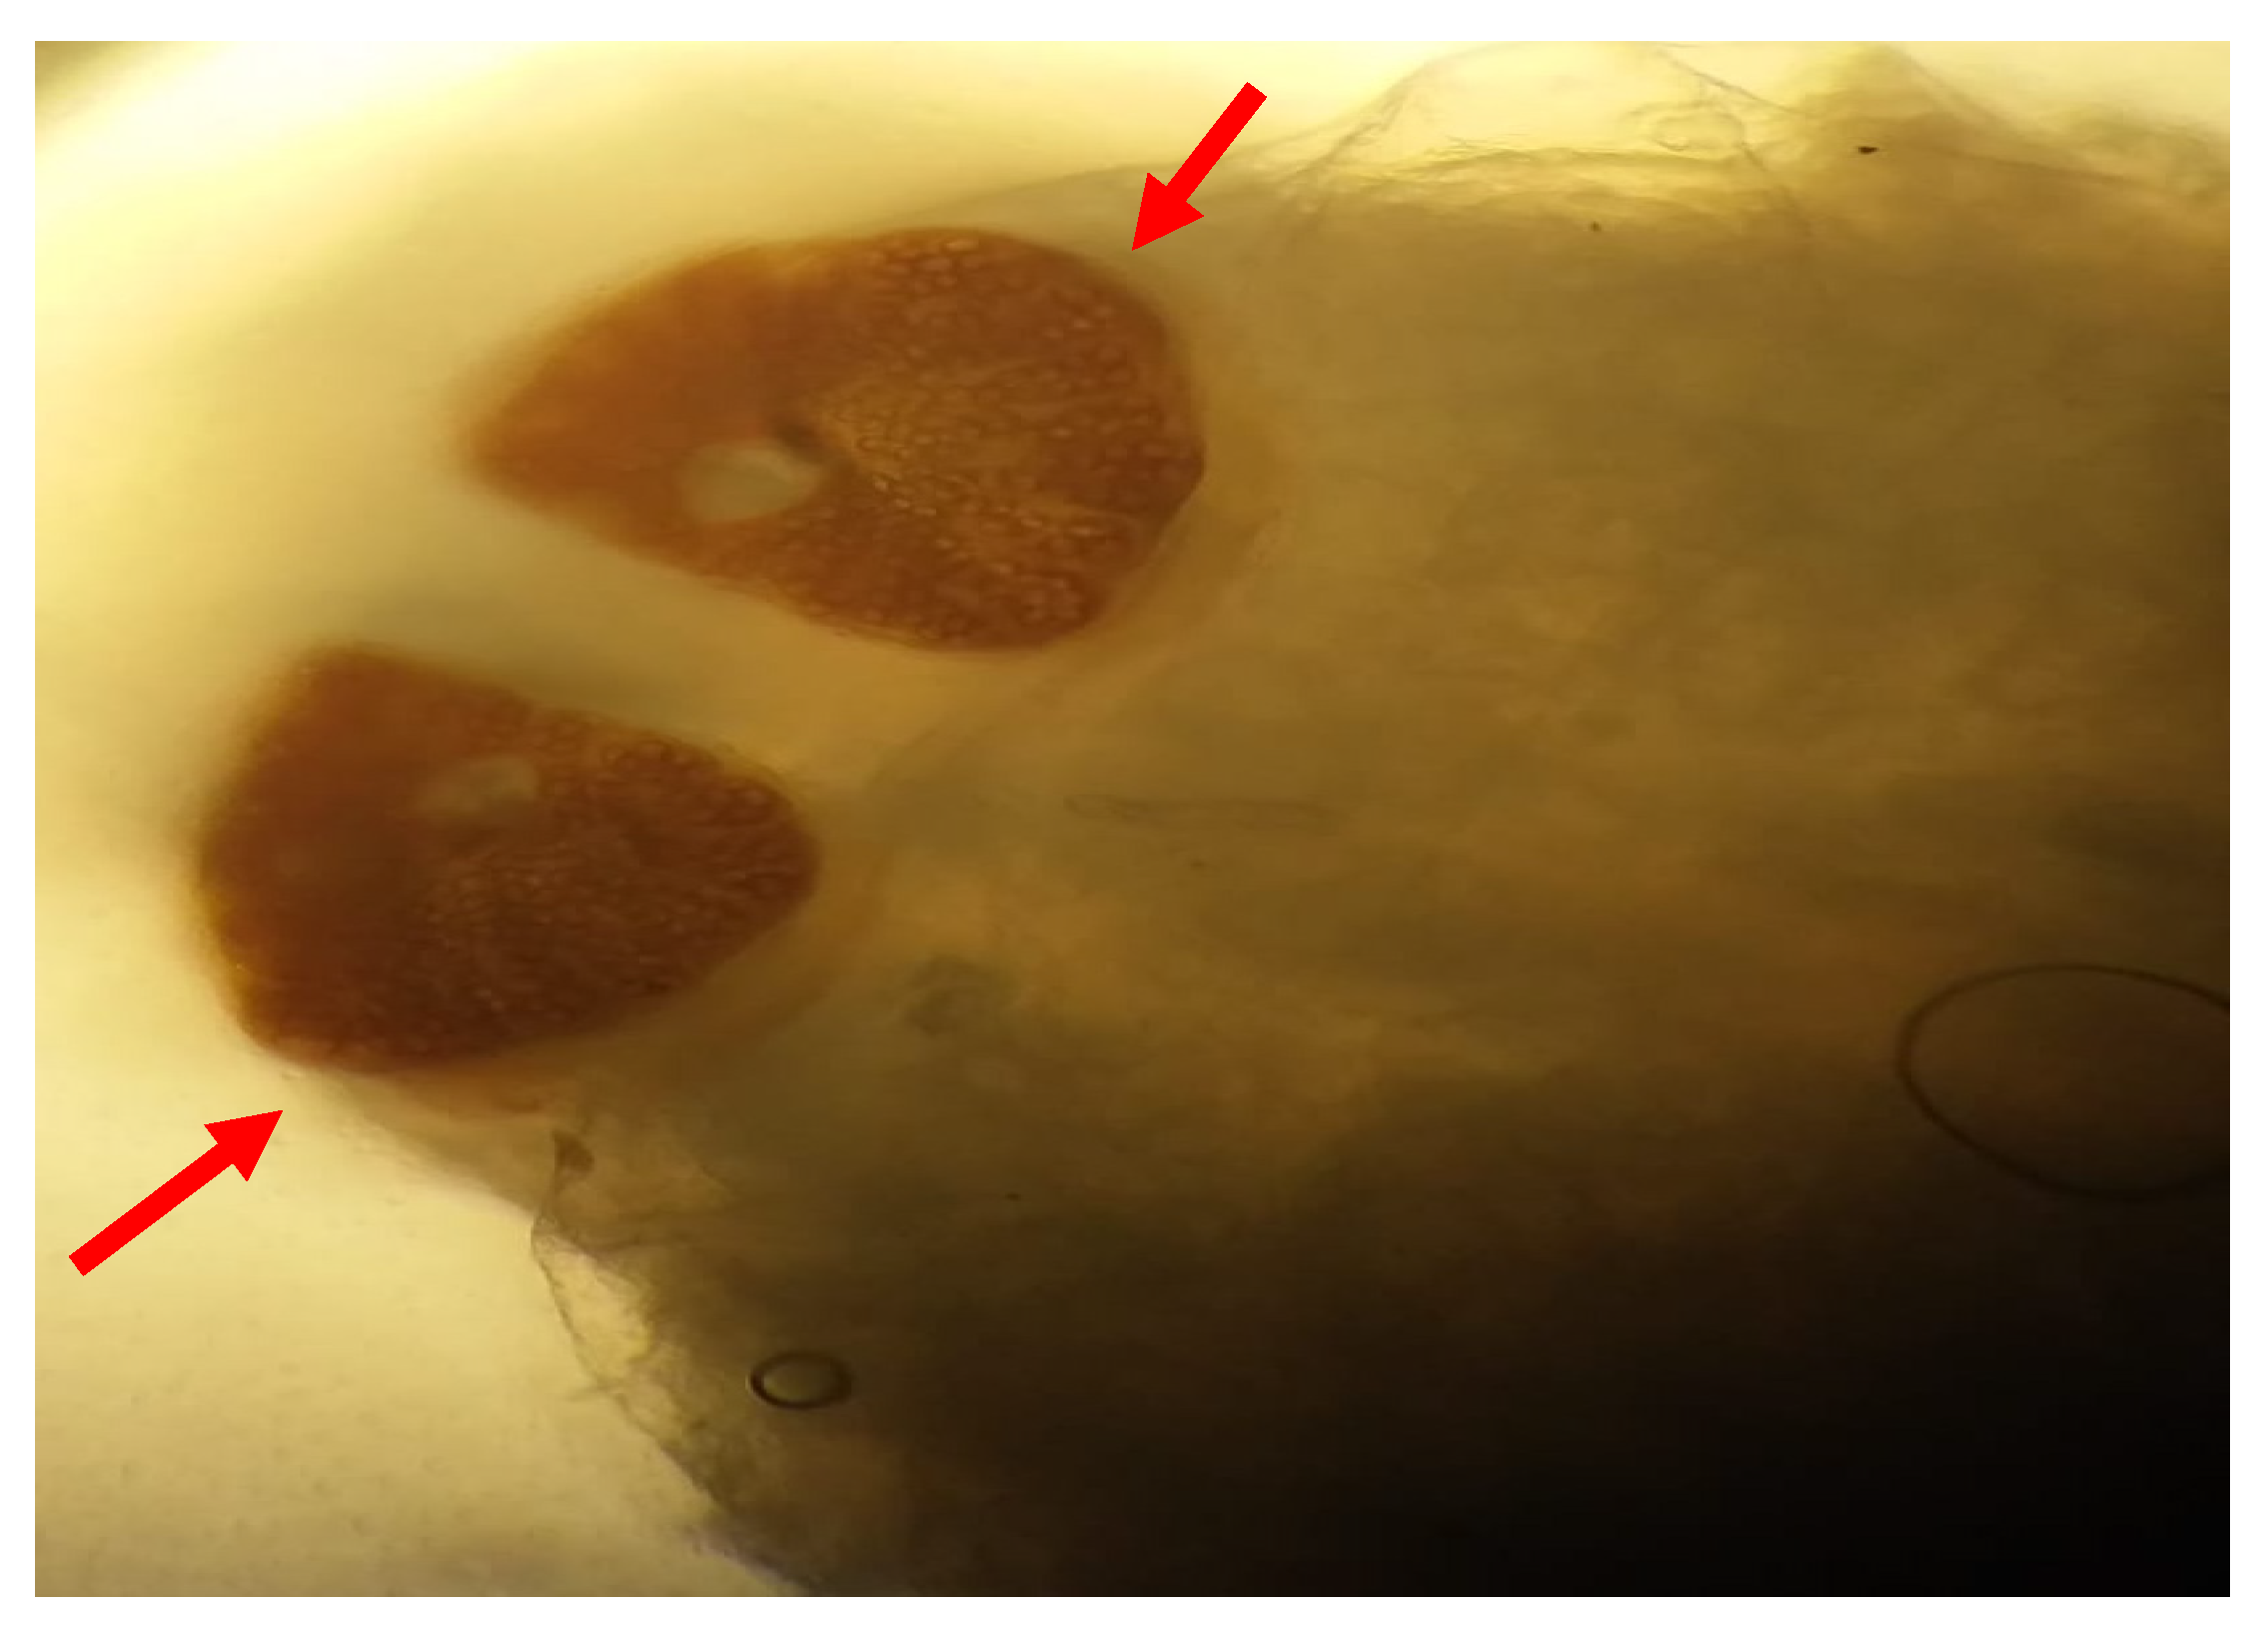

Macroscopic and microscopic examination of the larvae enabled us to identify the species Oestrus ovis according to Zumpt’s criteria. They were L2 stage larvae (between 5 and 6 mm in size) (Figure 1 and Figure 2). The larvae are semi-cylindrical in shape. The posterior respiratory stigmata are subcircular with a central knob and pierced by numerous pores (Figure 3).The pseudocephalon has two buccal hooks (Figure 4).

Figure 1. Oestrus ovis larva L2 stage (6mm); red arrow: posterior extremity; blue arrow: anterior extremity (case 4).

Figure 3. Posterior extremity of the larva: respiratory stigmata (red arrows) (case 4).